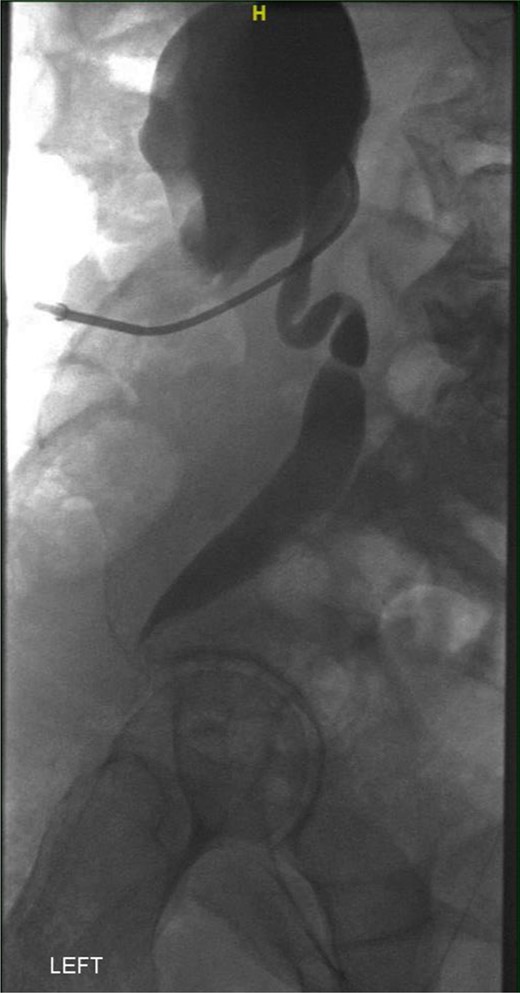

A week later, a left nephrostogram showed a capacious upper urinary tract with a deviated lower ureter which tapered in the pelvis with no filling defects seen above this level (Fig. 5). The appearances were in keeping with extrinsic compression. A week later, rigid cystoscopy, right-sided retrograde study, right JJ stent insertion and cystogram were performed. The left ureteric orifice could not be identified. The cystogram demonstrated no evidence of bladder herniation to the inguinal hernia (Fig. 6). Two months later, a non-contrast CT of the urinary tract demonstrated partial resolution of bilateral hydronephrosis, right-sided stent and left nephrostomy situated appropriately, persistence of left inguinoscrotal hernia and no other cause for ureteric compression. His eGFR was 34 mL/min when it was last checked a month prior to the non-contrast CT.

Left nephrostogram demonstrating tapering of the left ureter in the pelvis.